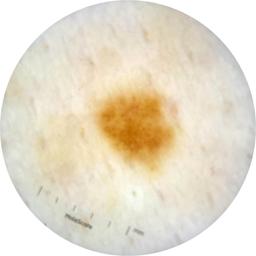

ISIC_9472333

Information

Dimensions

2057 x 2057

acquisition_day 230

age_approx 65

anatom_site_1 Trunk

anatom_site_2 Anterior trunk

anatom_site_general anterior torso

diagnosis_1 Benign

diagnosis_confirm_type single image expert consensus

image_type dermoscopic